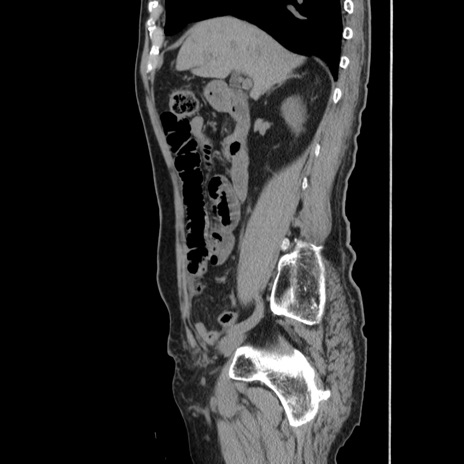

症例24(矢状断像)

冠状断像